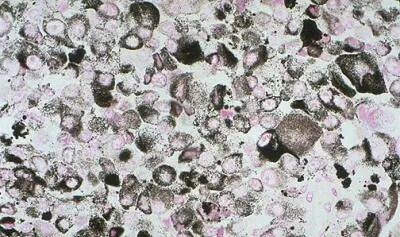

Melanin pigment incells of9.1. malignant melanoma, Fontana-Masson stain.